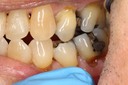

Photos of Clinical Operations

Mentors: Drs. Randy Allan, Greg Card, Peter Kearney

Clubs #44 and #50 joint meeting